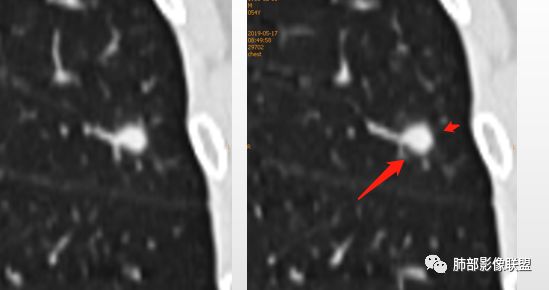

1、与炎性假瘤、恶性肿瘤鉴别:恶性肿瘤边缘膨隆,收缩也是毛毛糙糙的,炎性假瘤收缩力较强,边缘凹陷的多。隐球菌孤立结节收缩力弱,膨胀力也弱,与胸膜关系多为糊墙,部分有间隙。右边两幅可以看到胸膜增厚,胸膜下脂肪间隙增宽。晕中长毛刺,边缘平直,血管走行自然,鉴别肺癌。